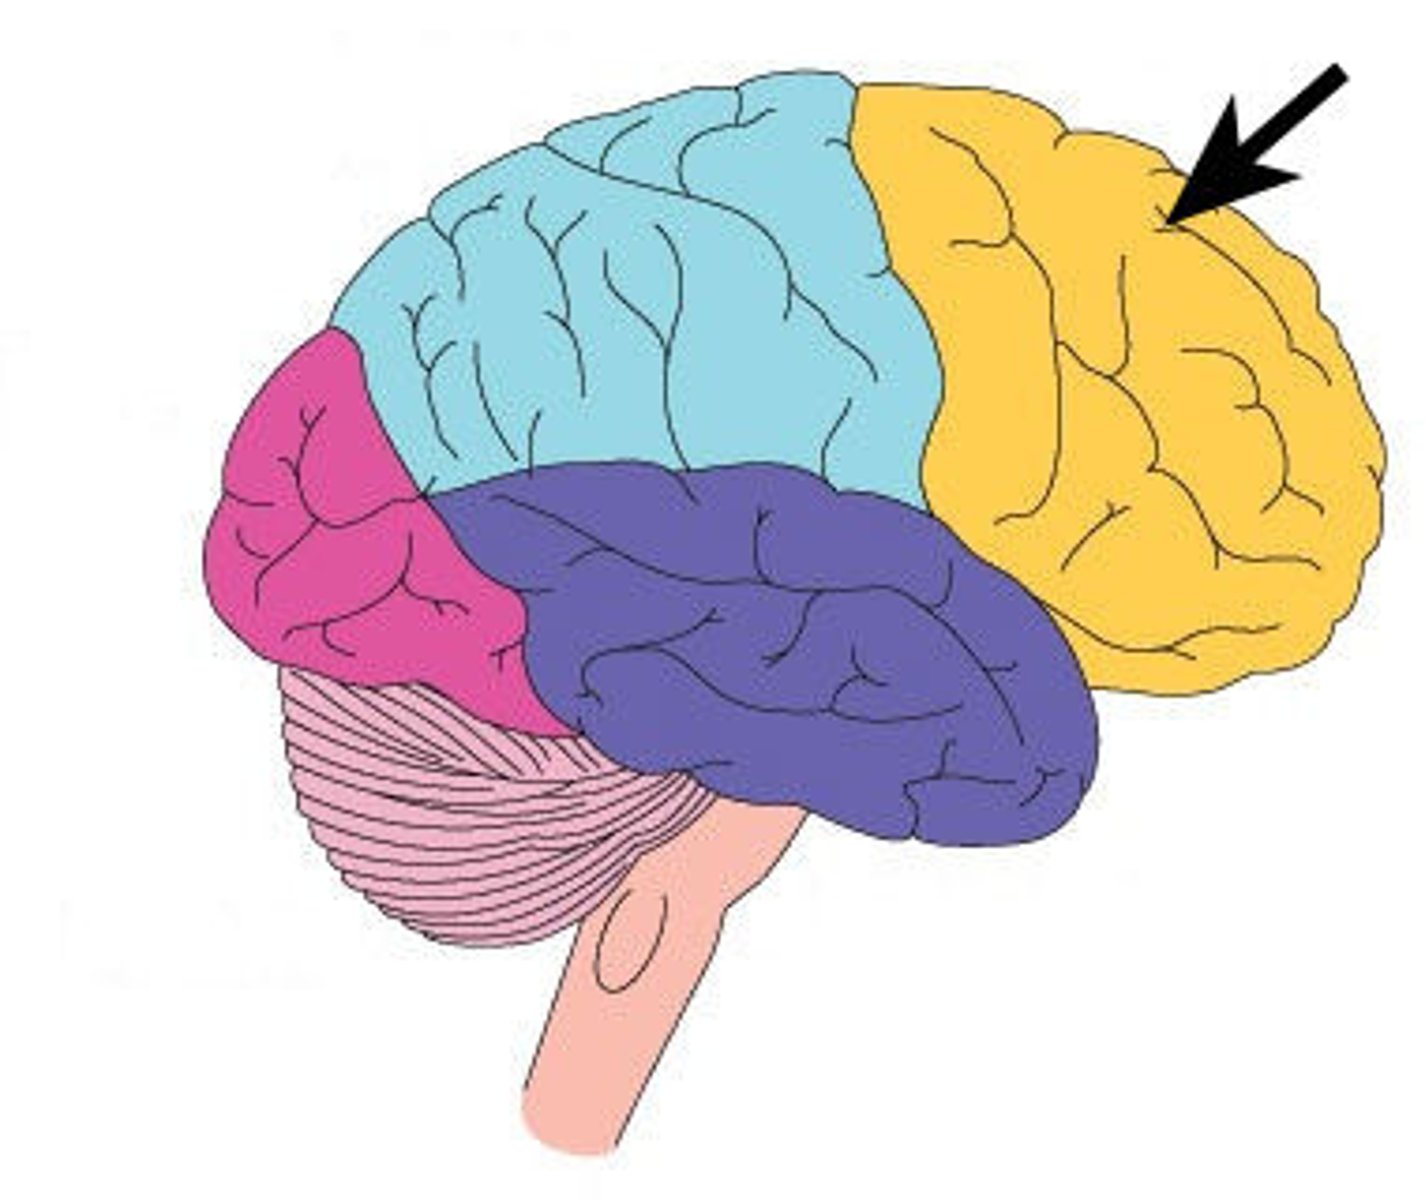

Surface lobes of the cerebrum

Frontal Lobe,

Temporal Lobe,

Parietal Lobe,

Occipital Lobe

Frontal Lobe

Primary (somatic) motor cortex

Temporal Lobe

Olfactory and Auditory input

Parietal Lobe

Reception and evaluation (integration) of sensory information except for smell, hearing, and vision

Occipital Lobe

Vision and integration of visual input

Frontal lobe: motor cortex

1) Controls precise or skilled voluntary movements of our skeletal muscles

2) Also learned motor skills (repititious or patterned nature) like playing an instrument or typing

3) Is contralateral: left primary motor cortex controls muscles on right side of body & vice versa